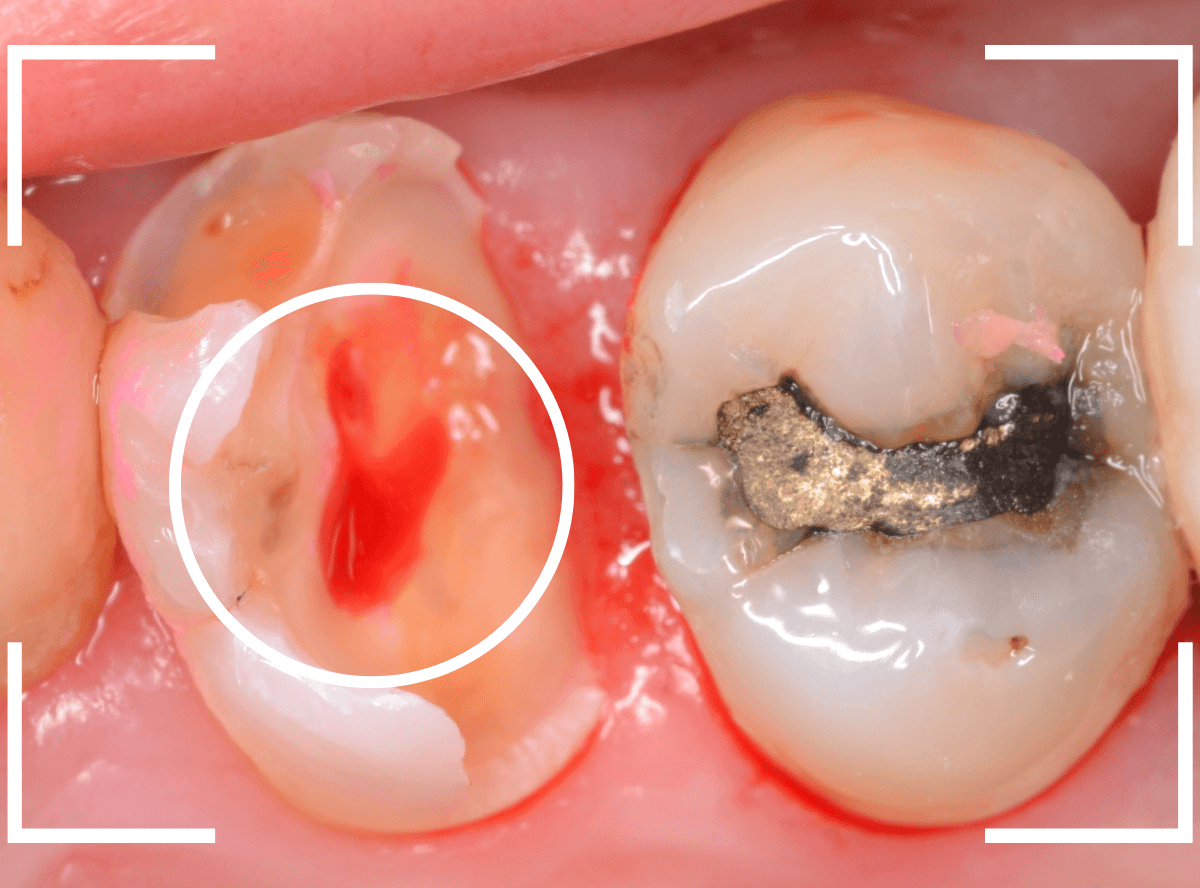

Case.14 インレーの下の歯肉まで広がった虫歯

「下の奥歯が噛むと痛む」という症状で来院された患者さんのケースです。

お口の中の状態を確認すると、奥歯の端に穴が開いているのが見えます。

やはり、奥歯の端が大きな虫歯になっています。

青いラインが歯の神経、赤いラインが虫歯です。

レントゲン写真上では虫歯が神経まで達しているように見えます。

これは、神経を取らないとダメかもしれません。

中のお薬も慎重に外して虫歯を除去します。

虫歯が深く、歯肉の下まで浸食していましたので、歯肉を部分切除し、虫歯を全て除去したところで、奇跡的に神経スレスレの状態でとどまっていました。

何とも言えませんが、神経を残せる可能性が出てきました。

虫歯が神経まで達していなくても、治療前から自発痛(何もしなくても痛い)があれば、神経をとらなければいけません。

今回は、そこまでの症状がありませんでしたので、患者さんと相談の上、神経を取らずに残す方法で様子を見る事になりました。

痛みが出ませんように。。。